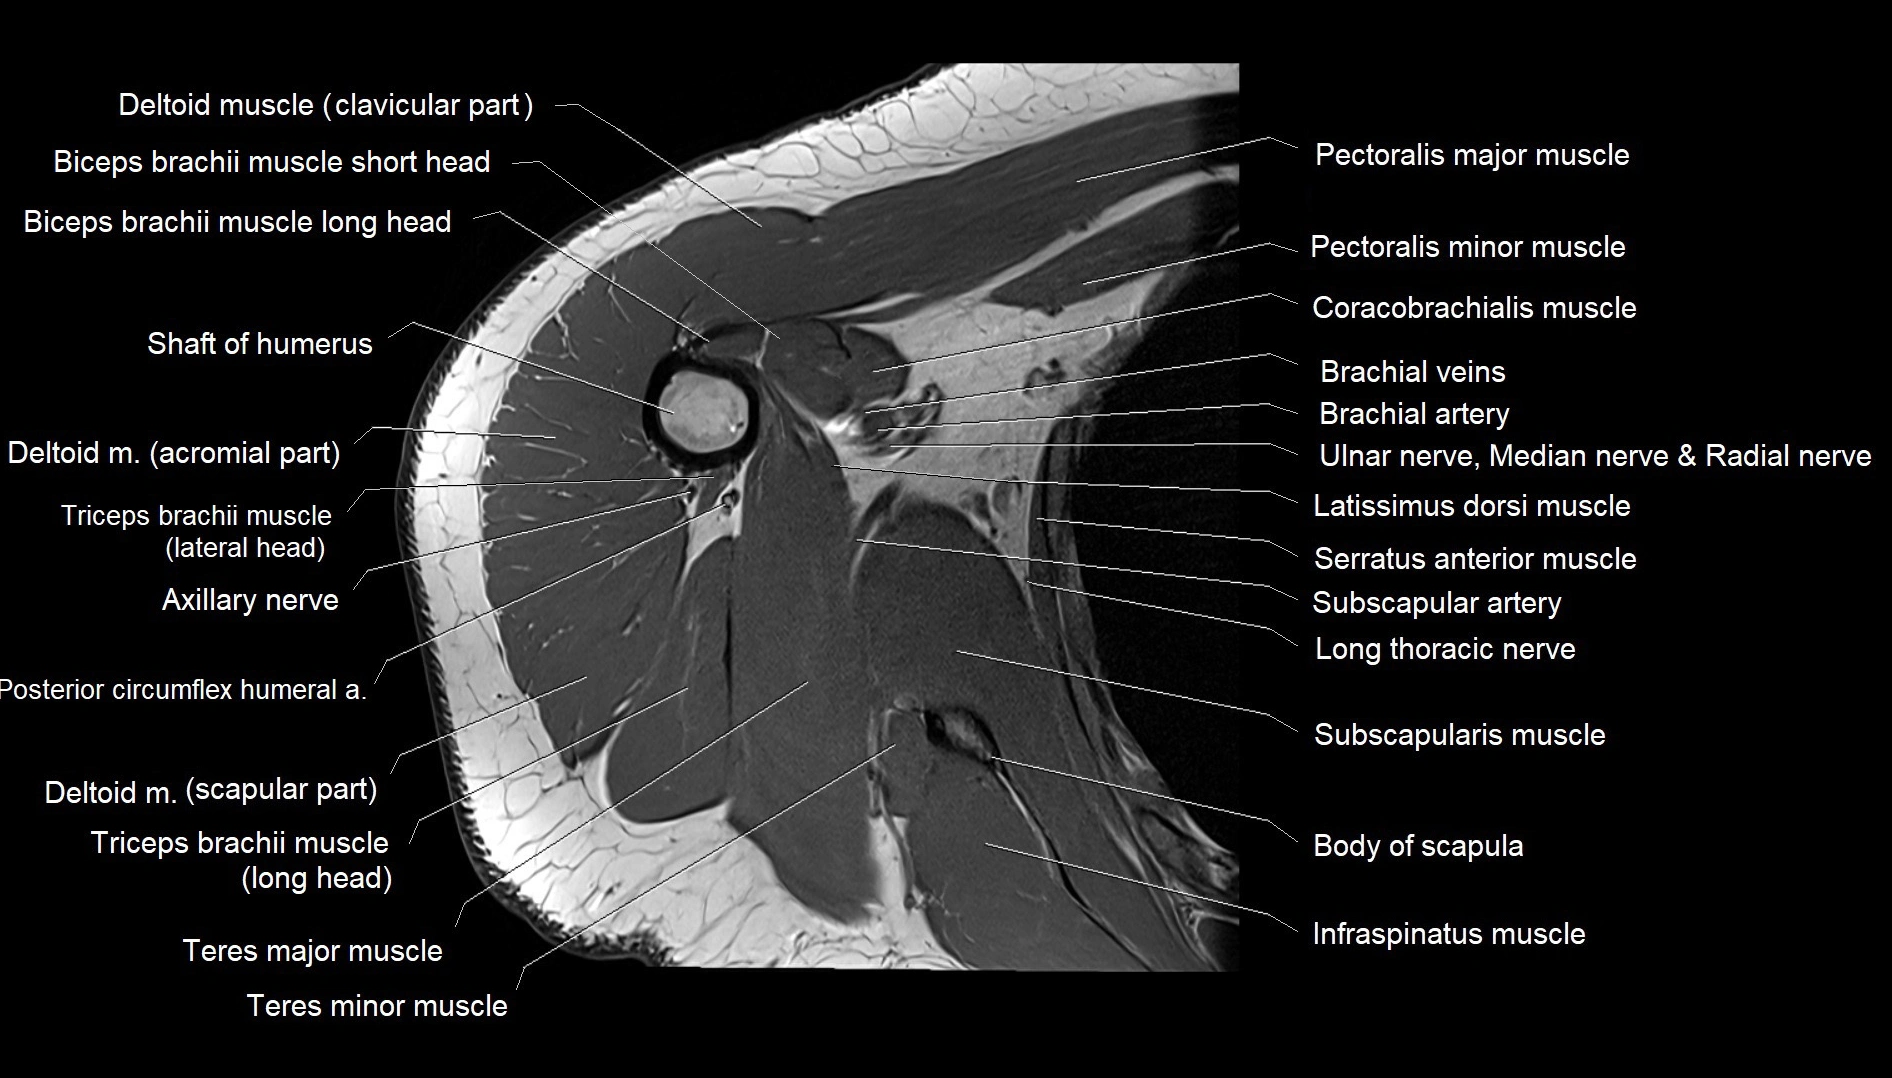

CT image

image